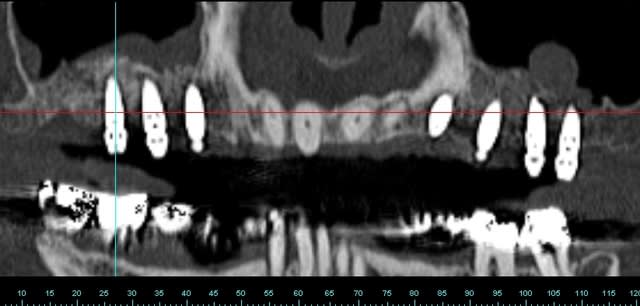

pour votre plaisir mon ami 8 mois d'écarts

fenêtre fermée par du vitalos pas de membrane technique "grosse ouverture"

ce qui ne me plait pas dans ton cas pxav c'est que tu n'as pas décollé la paroi médiale du sinus, tu fais une grosse fenêtre du coup tu te prives d'un apport vasculaire non négligeable.

la demande était radio à J et J+6 mois, pas "présentez un cas de comblement de sinus parfait".

Perso je trouve le résultat "correct" imagine si en plus j'avais fais un CS nickel...

j'ai une préférence pour le mode "ogival" plutôt que "mis à plat", pour des raisons mécaniques, (il me semble que le résultat est meilleur) mais j'ai peut etre tord.

Par contre, l'ouverture réduite ne me gêne pas au contraire, mais dans ce cas là le choix était large.